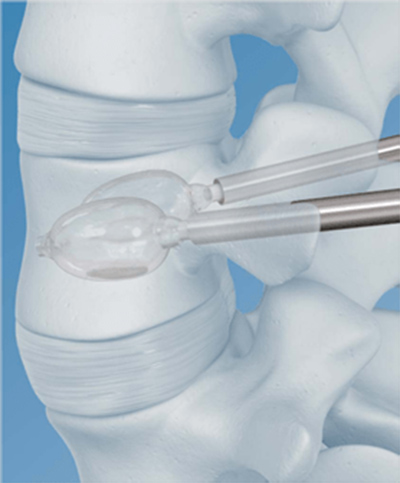

A variation of vertebroplasty is kyphoplasty, which uses a balloon that is inflated in the treated vertebral body to create a cavity within the vertebral cancellous bone (figure: kyphoplasty systems). The vertebroplasty cement is instilled directly into the newly created cavity after the balloon is deflated. Kyphoplasty and vertebroplasty have similar outcomes. Kyphoplasty is somewhat more expensive, but it can sometimes restore the height of the central aspect of the vertebral body by as much as 3 mm (Petscavage-Thomas, 2014). It is sometimes used for kyphotic deformity correction or in more complex cases of vertebral injury (McConnell, 2014).

Vertebral Body Balloon (VBB) System (DePuy Synthes) for vertebral augmentation procedures (kyphoplasty). © DePuy Synthes 2016. All rights reserved. Vertebral Body Balloon (VBB) System is a trademark of DePuy Synthes. |